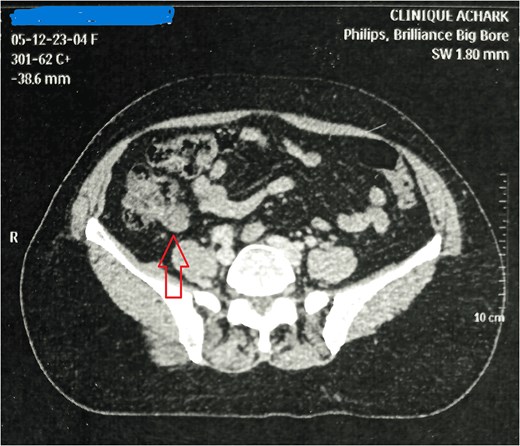

Mrs. A. H, aged 54, presented on December 2023, for further management of left breast invasive lobular carcinoma, for which she underwent lumpectomy with axillary lymph node dissection externally. The staging assessment, including abdominal computed tomography (CT) and magnetic resonance imaging (Fig. 1), revealed a mass in the right iliac fossa. On clinical examination, moderate tenderness was noted in the right iliac fossa, radiating to the left iliac fossa and right leg over the past few months. She had no complaints of vomiting or diarrhea. Her only medical history was controlled hypertension for 3 years with amlodipine and lifestyle modifications.

On CT scan, appendiceal mucocele appears as a rounded, well-defined mass at the cecal base with a thin wall and fine calcifications. Its wall may be thickened, irregular, with enhancing nodules suggestive of cystadenocarcinoma; however, there is no radiological sign to definitively confirm or exclude the malignancy of the underlying appendiceal tumor.